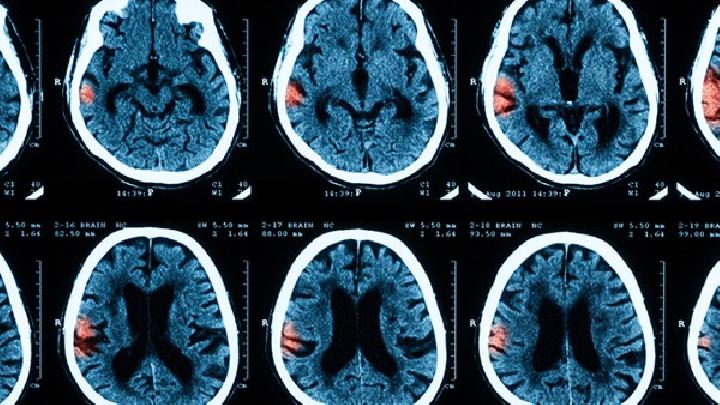

脑萎缩症状都有哪些?专家指出,老年性痴呆脑萎缩症状以隐袭起病、持续进行性的智能衰退为特征,记忆障碍通常显本病的首发症状,而后出现视空间技能损害、思维及判断能力障碍、语言障碍、计算障碍等大脑高级功能障碍以及行为异常等症状。

大脑萎缩的症状表现主要有记忆力减退、认知功能障碍、运动协调障碍、情绪性格改变。症状发展通常从早期轻微认知下降逐渐...